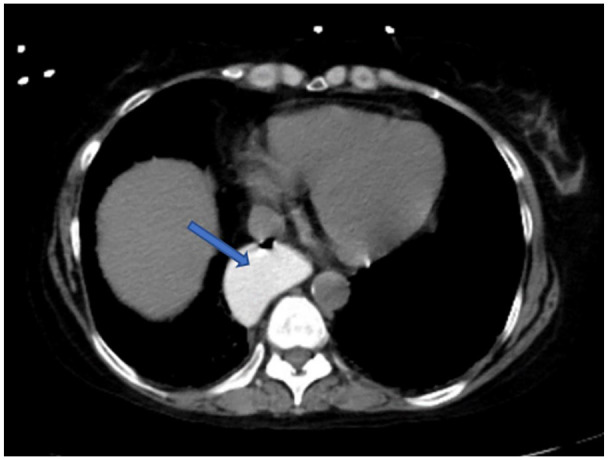

Scleroderma renal crisis is a rare, life-threatening complication of systemic sclerosis. It is characterized by pronounced hypertension, acute kidney injury, and thrombotic microangiopathy. Although its prevalence has decreased over the last decade, and death rates have declined since the introduction of treatment with Angiotensin converting enzyme (ACE)-inhibitors, it remains a challenge due to lack of prevention and rapid progression despite intervention in those who develop renal crisis. We present a 46-year-old female with history of rheumatoid arthritis and scleroderma who presented to the Emergency Department (ED) with complaints of a severe headache associated with nausea and vomiting that started earlier in the day. Patient presented with a blood pressure of 180/103 that did not improve with use of anti-hypertensive medications. Labs were remarkable for anemia and decreased renal function. A CT of the abdomen and pelvis without contrast demonstrated distention of distal esophagus with possible underlying esophageal dysmotility due to degree of distention and dependent areas of tractional bronchiectasis in the bilateral lower lobes that can be seen in the setting of early interstitial lung disease. Treatment with an ACE-inhibitor was initiated, with improvement in blood pressure and resolution of headache. This case demonstrates another rare case and illustrates the importance of rapid recognition and treatment.